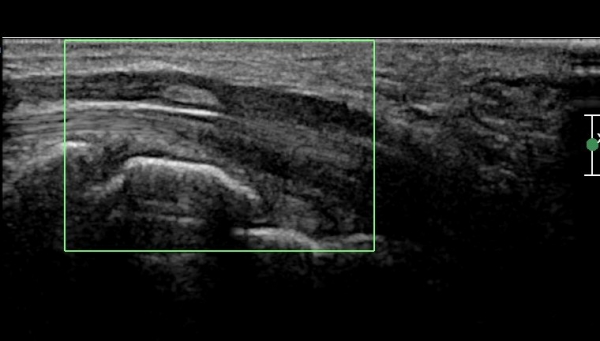

¼Õ¸ñ ºÎÀ§¿¡ Á¤Á߽Űæ Á¾´Ü¸é°Ë»ç»ó Á¤Á߽Ű泻 Ÿ¿øÇüÀÇ °í¿¡ÄÚ Á¾±«°¡ °üÂûµÇ´Âµ¥(»çÁø 3)